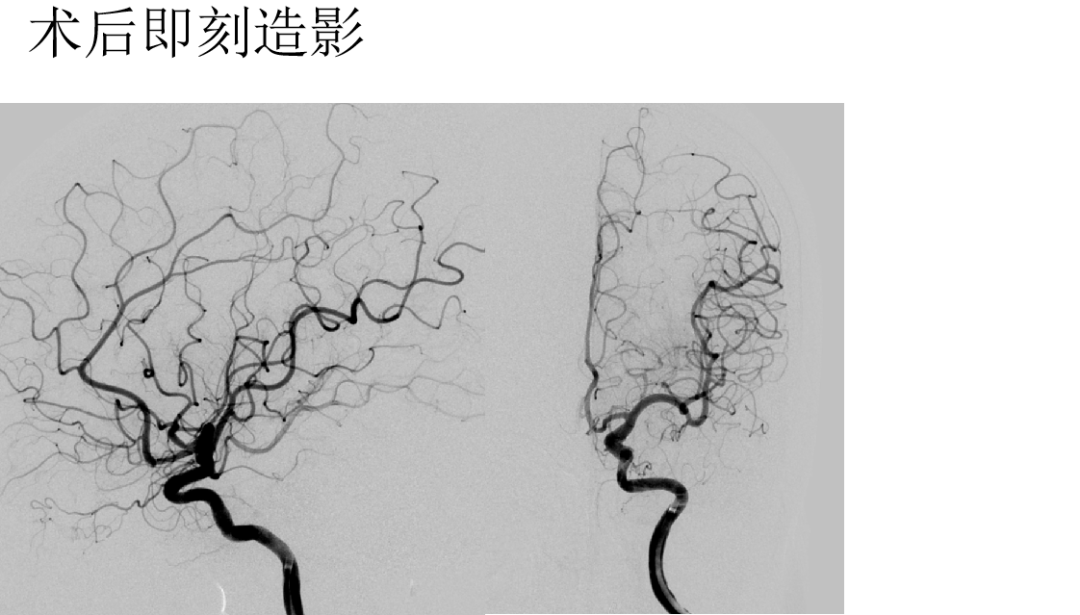

术后即刻DSA

Nuva 4.0x24,非常顺滑到位,稍维持张力,自主打开好;半释放保护瘤颈,填入泰杰3d36、Axium2d24、1.5x4;微导丝按摩支架。

动脉瘤内造影剂滞留

首次RICA An ped支架植入,瘤内造影剂明显滞留。

右侧ICA造影:动脉瘤正处于继续愈合状态,无需再处理

左侧C6多发动脉瘤